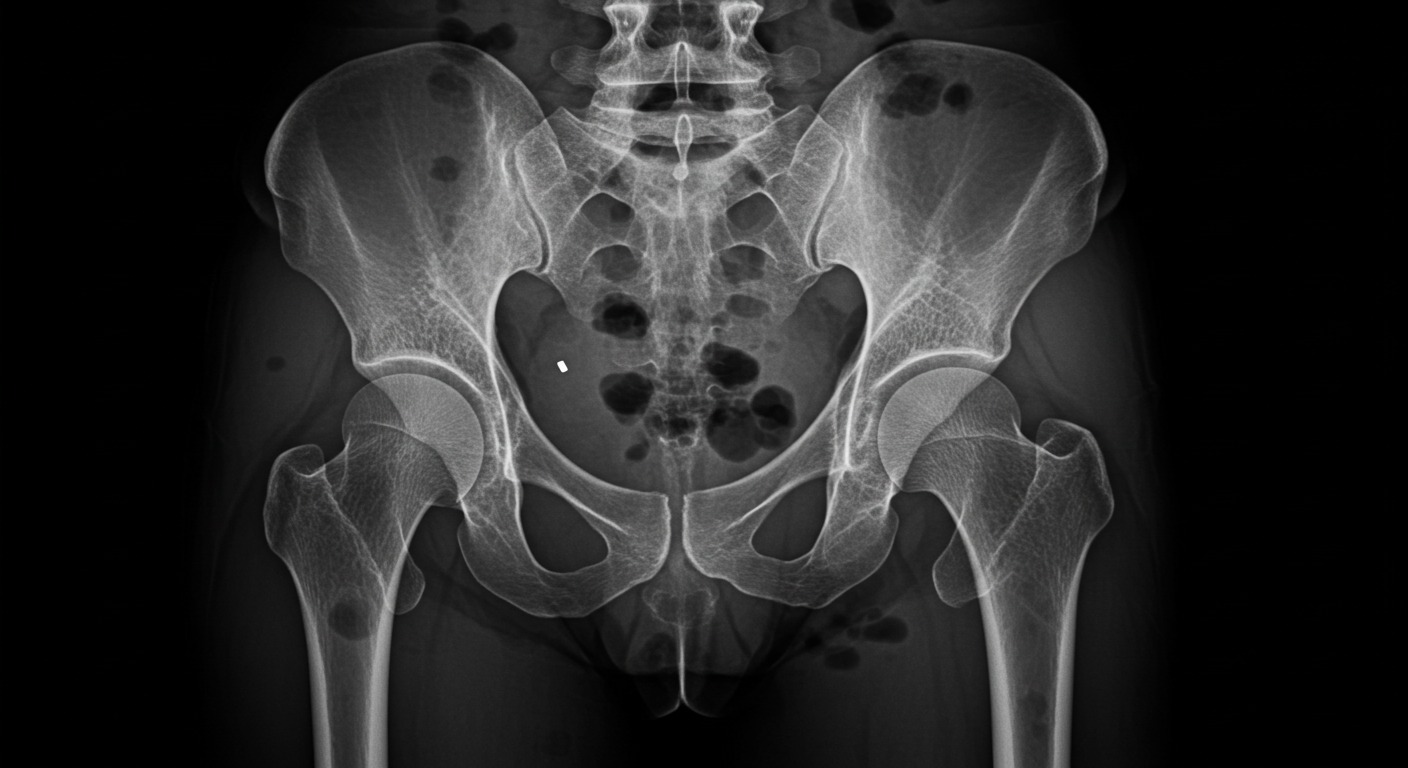

Bone Health

Articles tagged with "Bone Health"